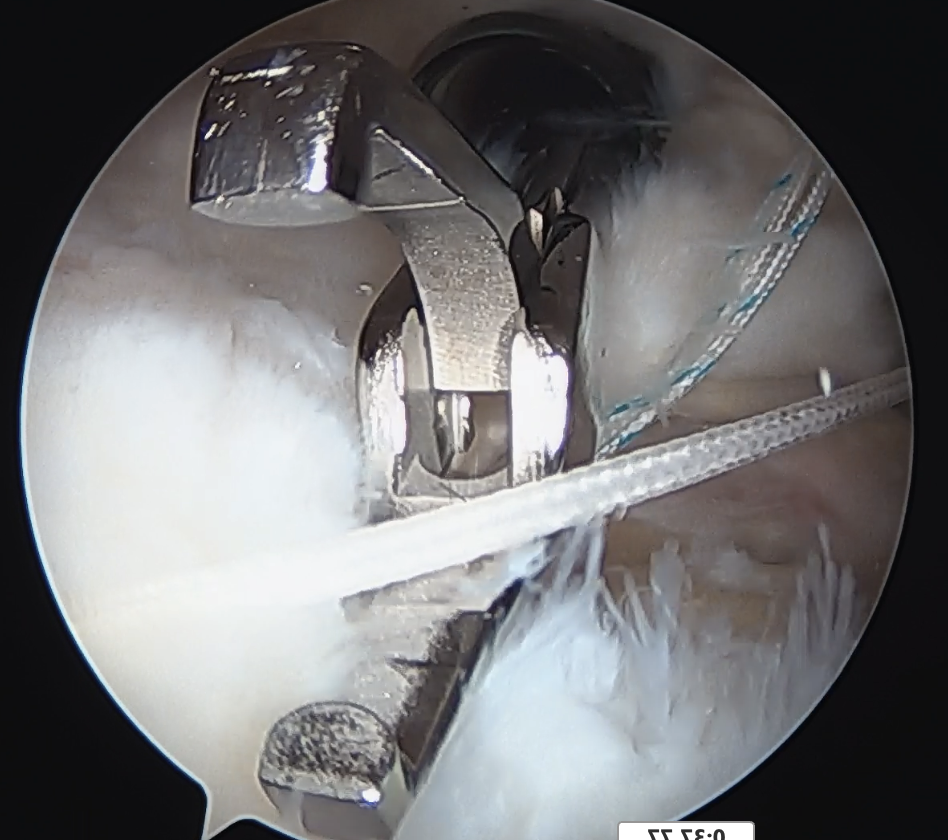

Medial row anchors

- inserted through additional stab incision for suture management

- just medial to articular cartilage

Pass sutures through medial cuff tendon

- camera posterior

- suture passer via lateral portal

- retrieve sutures through anterior portal

- repeat

- tie medial row